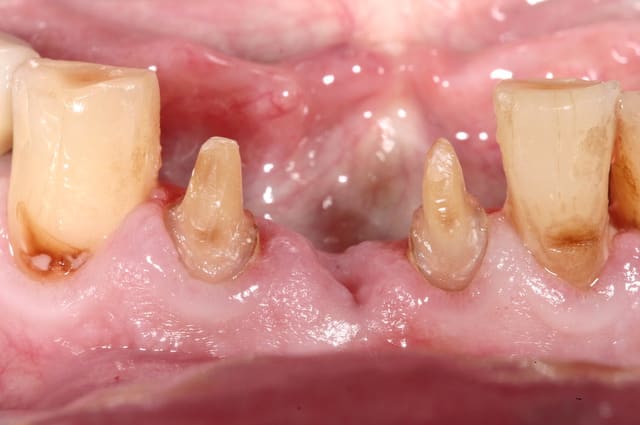

et ici ?? vous feriez quoi ?

32 et 42 pas mobiles

malheureusement, l'espace est réduit pour mettre deux implants.

comment avez vous déjà géré ce type de cas ??

le haut est déjà traité...